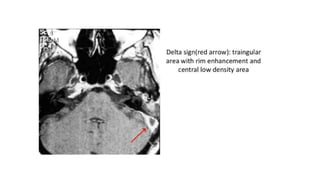

The document discusses lateral sinus thrombosis, also known as lateral sinus thrombosis or Otogenic suppurative thrombophlebitis, which is defined as the simultaneous presence of venous thrombosis and suppuration in the intracranial cavity. It is most commonly caused by b-hemolytic streptococcus and symptoms include nausea, vomiting, toxic and restless behavior, deep boring ear pain, and foul smelling blood tinged ear discharge. Management involves imaging, lumbar puncture of CSF to analyze volume, rate of formation, and composition.